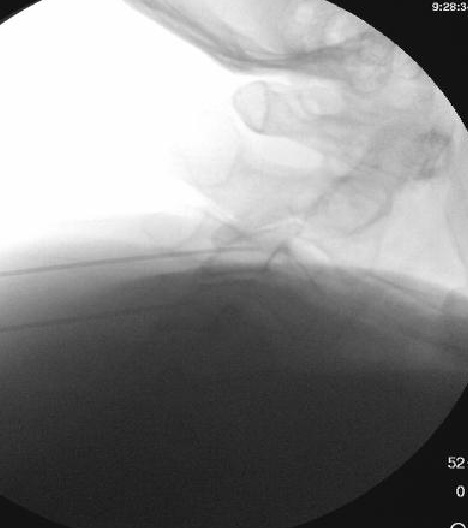

Only thing I do differently is aim for a touch more posterior placement of the needle. I try to make sure the very tip of the needle is at but not beyond the x in the image below. I also take a final lateral right before RFA. I think it helps reduce the frequency of neuritis to be a bit more posterior.

View attachment 395708

I appreciate the input, but I'm using a 10mm active tip and I'm burning quite a bit of MBN in that pic right there. Going more posterior theoretically means I'm getting less of it.

Based on some discussion on here a few years back, I tried burning 1/2 way along the pillar rather than anterior edge, but felt like I saw an immediate increase in neuritis. I suspect there are at least 2 different causes. Some neuritis comes from burning nerves with a sensory input to the skin, unavoidable, but some comes from being a little off target and only irritating rather than completely burning a medial branch nerve.